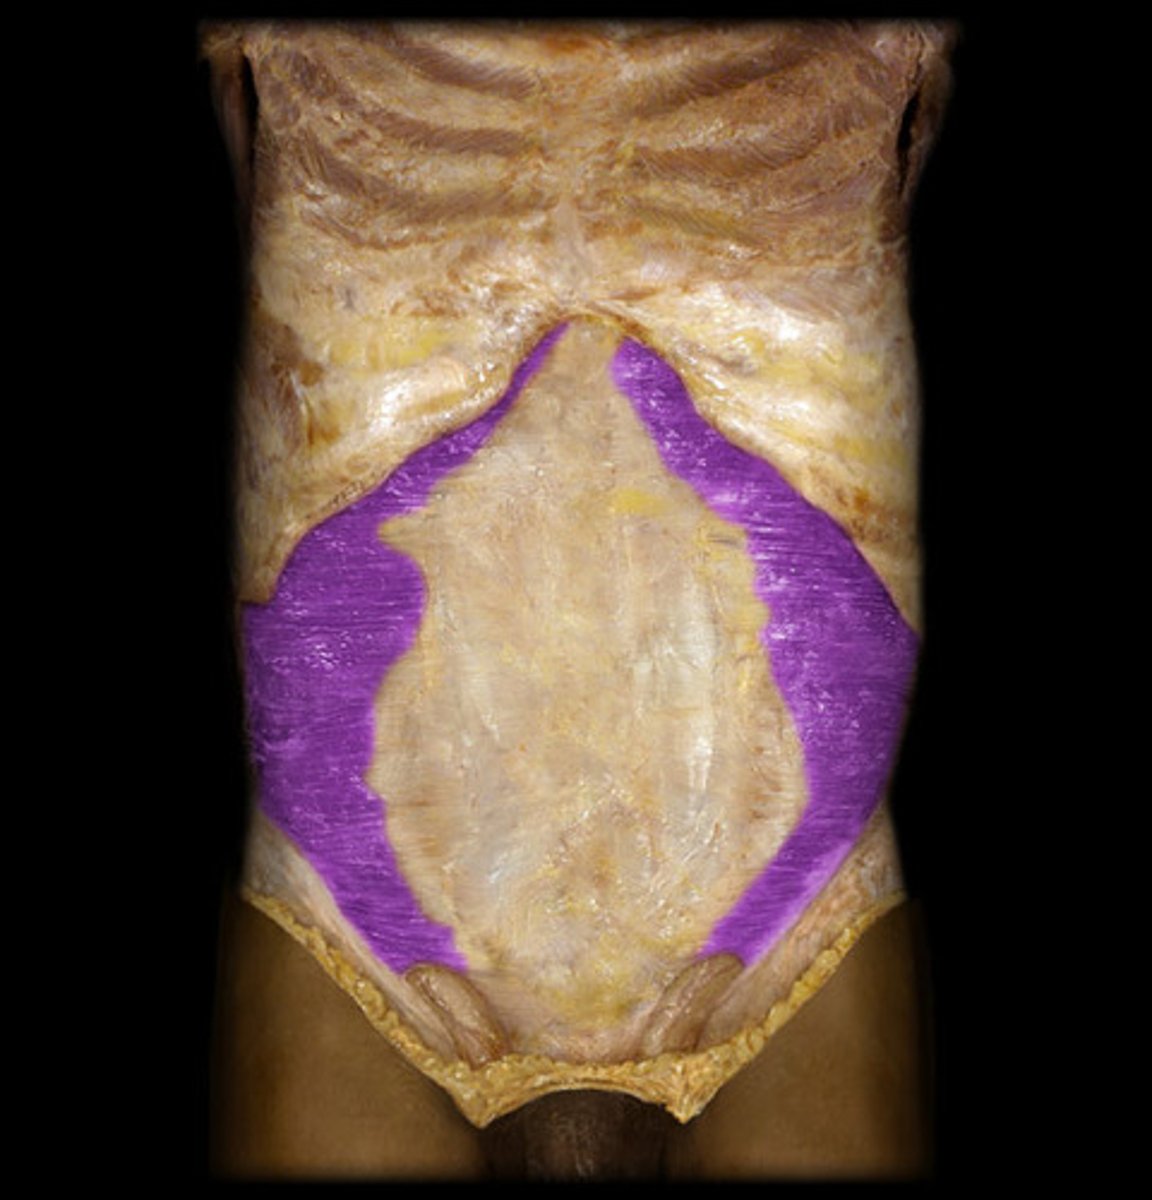

External Obliques

Origin: Ribs 5-12

Insertion: Anterior half of iliac crest; symphsis and superior margin of pubis

Action: supports viscera; stabilizes vertebral column; maintains posture

Internal Obliques

Origin: Inguinal ligaments; iliac crest; thoracolumbar fascia

Insertion: ribs 10-12; costal cartilages 7-10; pubis

Action: Support viscera' stabilizes vertebral column; maintains posture; unilateral contraction causes ipsilateral rotation of waist

Transverse Abdominus

Origin: Inguinal ligament; iliac crest; thoracolumbar fascia; costal cartilages 7-12

Insertion: Linea alba; pubis; aponeurosis of internal oblique

Action: Compresses abdominal contents; does not contribute to vertebral column movements